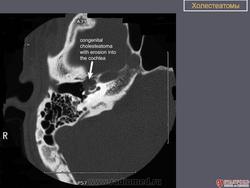

Диагностика холестеатомы представляет определенные трудности. Основными методами выявления холестеатомы последние несколько десятилетий остаются отоскопия (отомикроскопия) и рентгенологические методы (рентгенография в различных укладках и компьютерная томография). Компьютерная томография височных костей позволяет диагностировать холестеатому намного чаще, чем обычная рентгенография, однако степень достоверности данной диагностики остается невысокой, так как плотность холестеатомы практически соответствует плотности грануляционной ткани. Поэтому чувствительность метода КТ в диагностике холестеатомы составляет всего 71% при специфичности 55% [50]. Кроме того, следует учитывать, что указанный метод требует не только дорогостоящего оборудования, но и высококвалифицированных рентгенологов со специальной подготовкой, позволяющей им правильно интерпретировать полученные результаты.

ID: 9408 Cholesteatoma Dr Frank Gaillard - 14 Apr 2010 HistologyFragments of keratin debris and benign squamous epithelium, con...